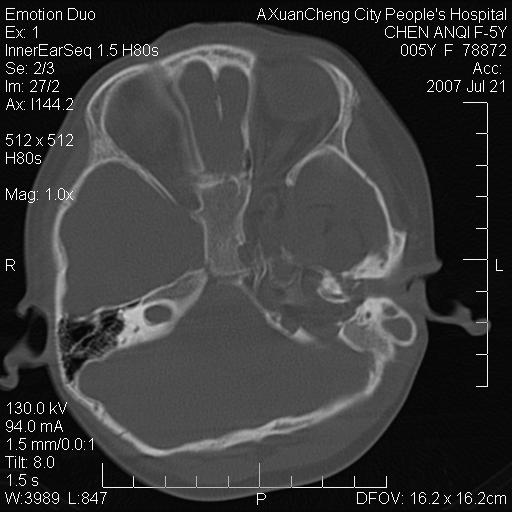

标题: PED0273:5岁,左耳流脓痛疼一周,颅底骨质破坏 [打印本页]

标题: PED0273:5岁,左耳流脓痛疼一周,颅底骨质破坏

患儿5岁,左耳流脓痛疼一周,左外耳道肉芽组织填塞 软组织窗显示病灶内结节状低密度影为气体密度

左侧中耳炎并胆脂瘤,左颞骨岩部骨质破坏并颅内感染积气。